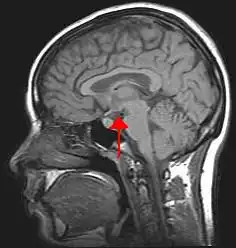

Location of the human hypothalamus

Location of the hypothalamus (cyan) in relation to the pituitary and to the rest of the brain